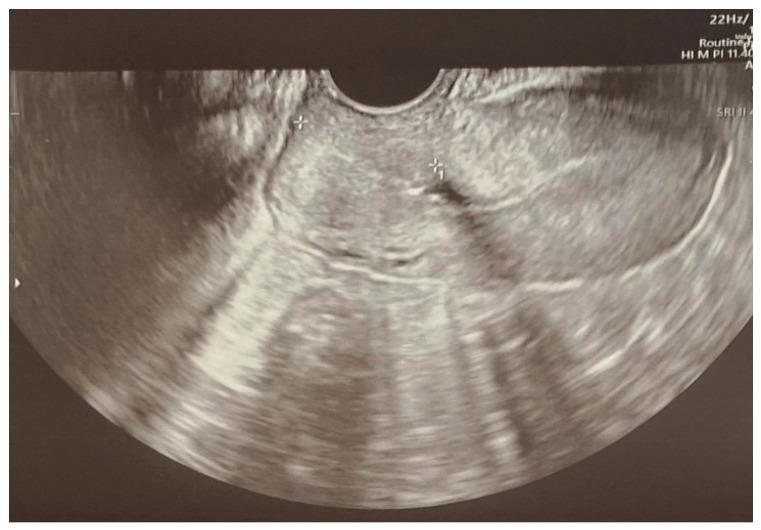

Intracranial hemorrhage is a rare yet potentially devastating event during pregnancy with a significant risk of maternal and fetal mortality and morbidity. The risk of intracranial hemorrhage increases during the third trimester of pregnancy and is greatest during labor and the postpartum period. Interdisciplinary diagnosis and treatment of the pregnant population often begins in the emergency department setting and is key to increasing patient survival rates through immediate and adequate treatment, including emergency medicine, neurosurgical and obstetrical procedures. A unique case report with a diagnostic pathway for intracranial hemorrhage due to eclampsia in a primipara at 24 weeks of gestation is presented, illustrating potential diagnostic dilemmas as the patient rapidly progresses into hemolysis, elevated liver enzymes and low platelets syndrome. A literature review was conducted to uncover the etiology of intracranial hemorrhage during pregnancy, as well as its diagnostic challenges and treatment. Pregnancy should not be viewed as a barrier to performing angiography or endovascular treatment for vascular causes of intracranial hemorrhage. Patient transport to a tertiary reference center and the interdisciplinary cooperation of specialists are key to achieving correct and rapid treatment. Continuous prevention of preeclampsia and patient education are necessary to decrease the incidence of eclampsia and its complications. Key message: Intracranial hemorrhage and eclampsia in pregnant patients are rare yet may result in high rates of maternal and fetal morbidity and mortality. The diagnostic process is difficult and requires interdisciplinary cooperation to start the correct treatment immediately.

颅内出血是孕期罕见但可能具有毁灭性的事件,母婴死亡和发病风险显著。颅内出血风险在妊娠晚期增加,在分娩期和产后期间最高。对孕妇群体的多学科诊断和治疗通常在急诊科开始,通过包括急诊医学、神经外科和产科手术在内的及时且充分的治疗来提高患者存活率是关键。本文呈现了一例独特病例报告,涉及一名妊娠24周初产妇因子痫导致颅内出血的诊断路径,该病例展示了随着患者迅速发展为溶血、肝酶升高和血小板减少综合征时可能出现的诊断困境。进行了文献综述以揭示孕期颅内出血的病因及其诊断挑战和治疗方法。不应将妊娠视为对因颅内出血的血管病因进行血管造影或血管内治疗的障碍。将患者转运至三级转诊中心以及专家的多学科合作是实现正确快速治疗的关键。持续预防子痫前期和对患者进行教育对于降低子痫及其并发症的发生率是必要的。关键信息:孕妇颅内出血和子痫罕见,但可能导致母婴高发病率和死亡率。诊断过程困难,需要多学科合作以立即开始正确治疗。